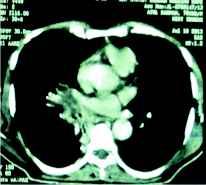

Once the diagnosis was made, considering his impaired renal function and the financial status, he was put on posaconazole in the dose of 200 mg 12 hourly with concomitant monitoring of blood counts, liver and renal function tests. The patient responded dramatically and his fever subsided after 4th day with reduction of dyspnoea and return of the physical well being. He was discharged on posaconazole 200 mg 12 hourly. Repeat CT scan of the thorax after 3 weeks of therapy revealed mark resolution of the lesions (figure 3).

Figure 3: A repeat CT cut at the same area reveals significant resolution of the mass lesion after treatment with posaconazole.